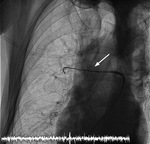

Efekt Bernoulliego

Ryc. 1. Angiografia prawej tętnicy płucnej – widoczne masywne skrzepliny powodujące upośledzenie przepływu krwi przez łożysko płucne (górny płat – białe strzałki).

– Przez dostęp centralny od prawej żyły udowej wprowadziliśmy do pnia płucnego oraz kolejno lewej i prawej tętnicy płucnej cewnik diagnostyczny, wykonując wstępną angiografię. Następnie przez cewnik wiodący po prowadniku wprowadziliśmy do tętnicy płucnej system do trombektomii (ryc. 2). Jego działanie oparte jest na równaniu Bernoulliego. Równanie to opisuje zjawisko, w którym im większa jest prędkość cieczy, tym mniejsze jest jej ciśnienie. Wewnątrz cewnika nie ma elementów mechanicznych, jedynie strumień soli fizjologicznej rozpędzonej do ponad 500 km/h. W ten sposób powstaje w okolicy cewnika, czyli jego części roboczej, niemal próżnia, w wyniku której pod wpływem różnicy ciśnień dochodzi do rozdrobnienia skrzepliny, a następnie częściowego odessania jej drobnych fragmentów – tłumaczy lek. Dominik Wretowski.